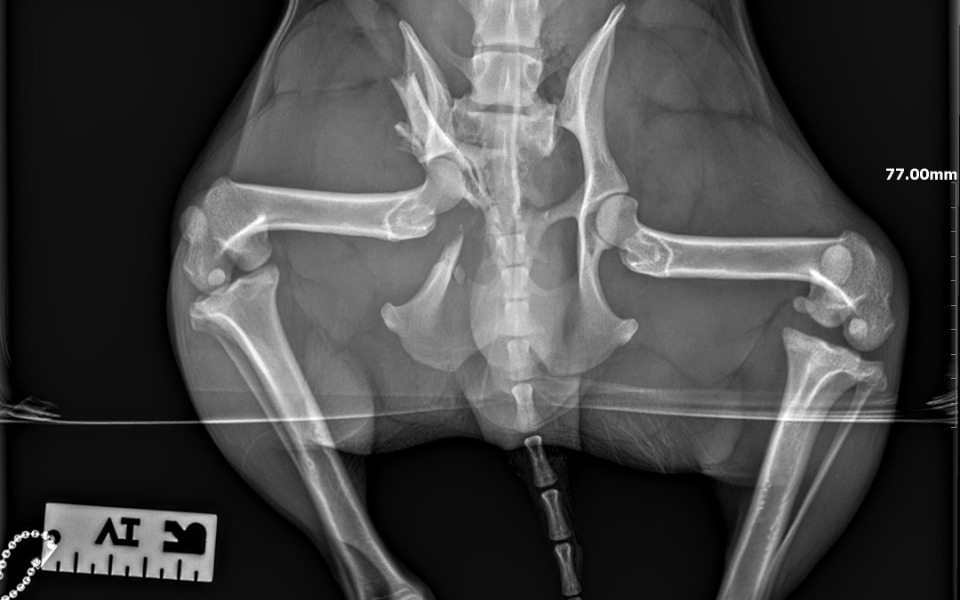

Kochani! Piesek został potrącony oczywiście sprawca nie raczył sprawdzić czy piesek żyje... Zostawił go na drodze narażając na rozjechanie i pewną śmierć. Właściciel psa prawdopodobnie zostawił go i wyjechał, a piesek błąkał się po wsi... aż się wydarzyło... "Znajdek" został zawieziony do lecznicy i okazało się, że ma złamanie wieloodłamowe przezpanewkowe prawostronne, zwichnięcie biodrowo-krzyżowe lewostronne, uraz glowy, urazy wielonarządowe. Koszt operacji chirurgicznej (śrubowanie) to kilka tysięcy, dodatkowo jeszcze koszty rehabilitacji. Dodatkowo czas nagli bo z podjęciem operacji nie można czekać.